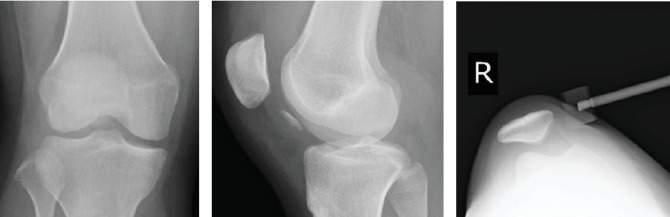

一个健康的16岁女孩在髌骨脱位后出现股骨外侧髁(LFC)后侧骨软骨骨折。骨软骨碎片固定及髌股内侧韧带重建均取得满意效果。据我们所知,这只是第三例报道的后LFC骨软骨骨折病例。然而,我们认为损伤机制与前两个病例不同。

A healthy 16-year-old girl presented with an osteochondral fracture of the posterior aspect of the lateral femoral condyle (LFC) following patellar dislocation. Satisfactory results were obtained with osteochondral fragment fixation and medial patellofemoral ligament (MPFL) reconstruction. To the best of our knowledge, this is only the third reported case of an osteochondral fracture of the posterior LFC. However, we believe that the mechanism of injury differed from that in the two previous cases.